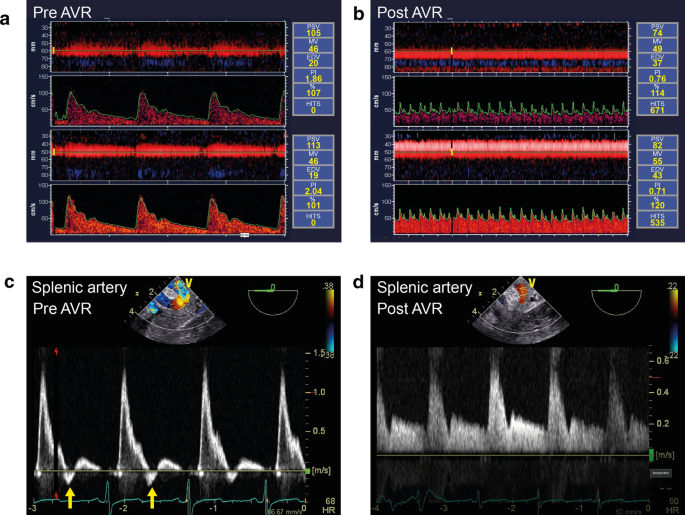

This case shows the utility of combining TCD with cerebral and somatic NIRS. Initially, the isolated cerebral desaturation that we saw was secondary to excessive ventilation resulting in hypocapnia. In that situation, somatic NIRS was normal indicating that the problem was affecting cerebral vasculature and was not from a systemic low flow state. Although hypocapnia has been associated with a reduction in mean cerebral blood velocity from 2.5 to 3.9% per mmHg,10 those TCD changes are not as easily detected as they are with NIRS, as this amount of change is within the variation that can be seen depending on other cerebral autoregulation factors.11 On the other hand, if both cerebral and somatic desaturation occur, then a systemic low flow state such as heart failure or bleeding should be expected as the underlying etiology. In a systemic low flow situation, both cerebral blood flow estimated from TCD velocities and NIRS would have been reduced.12 In our experience, air emboli detected by TCD will often be observed before RV failure becomes apparent on TEE examination, as in the current case, or before the appearance of electrocardiographic changes of ischemia.13 Preferential embolization of air in the right coronary artery can be explained by the non-dependent position of its ostium in the aortic root. Cerebral hypoperfusion would be suspected if mean, systolic, and diastolic cerebral blood velocities of the middle cerebral artery are reduced as opposed to venous congestion where only diastolic cerebral blood velocities will be attenuated with the systolic values remaining unchanged.14 During venous congestion and elevation in central venous pressure, diastolic cerebral blood velocity from TCD will be reduced and the pulsatility index ([systolic velocities – diastolic velocities]/mean velocities) (normal: 0.81–0.97) increased,10,15 with reductions in both cerebral and somatic NIRS values. Similar signals will be observed with intracranial hypertension,16 although somatic NIRS values would remain normal. Chronic aortic regurgitation with reduced aortic diastolic pressure can also be associated with elevated pulsatility index regardless of NIRS value.17 When combined cerebral and somatic NIRS desaturations occur, the mechanism is not cerebral. Similarly, TCD can also be interpreted with both cerebral and somatic values (Fig. 2). If Doppler interrogation of a somatic artery like the splenic artery (Fig. 2c)13 shows reduced diastolic blood velocity and elevated pulsatility index, then the abnormal cerebral TCD is not the result of an intracranial process but could be secondary to chronic aortic regurgitation, for example. Finally, if both the NIRS and TCD signals are normal but the radial arterial pressure is reduced, pseudo radial hypotension could explain this situation, as encountered here after the first weaning attempt.18 Systolic radial-to-femoral gradients ≥ 25 mmHg and MAP gradients ≥ 10 mmHg can be observed in one third of cardiac surgical patients.19 A proposed approach of combining cerebral and somatic NIRS to TCD is summarized in Fig. 3. Further validation in a larger patient cohort is required.

Fig. 2

figure 2

Transcranial Doppler-derived blood velocity (A) before and (B) after aortic valve repair (AVR) in a 69-yr-old man with severe chronic aortic regurgitation. Note the reduced end-diastolic velocities (EDV) and the elevated pulsatility index (PI) from 1.86 and 2.04 (normal: 0.8–1.2) in the left and right middle cerebral artery which normalized after AVR. (C) Simultaneously obtained splenic artery Doppler velocities from a transgastric abdominal ultrasound. Note the reversed diastolic velocities (arrows) before AVR. (D) After AVR, increased diastolic velocities were observed. % = percentage mean velocity (MV) values compared with baseline; ESV = end-systolic velocity; PSV = peak systolic velocity; HITS = high-intensity transient signals